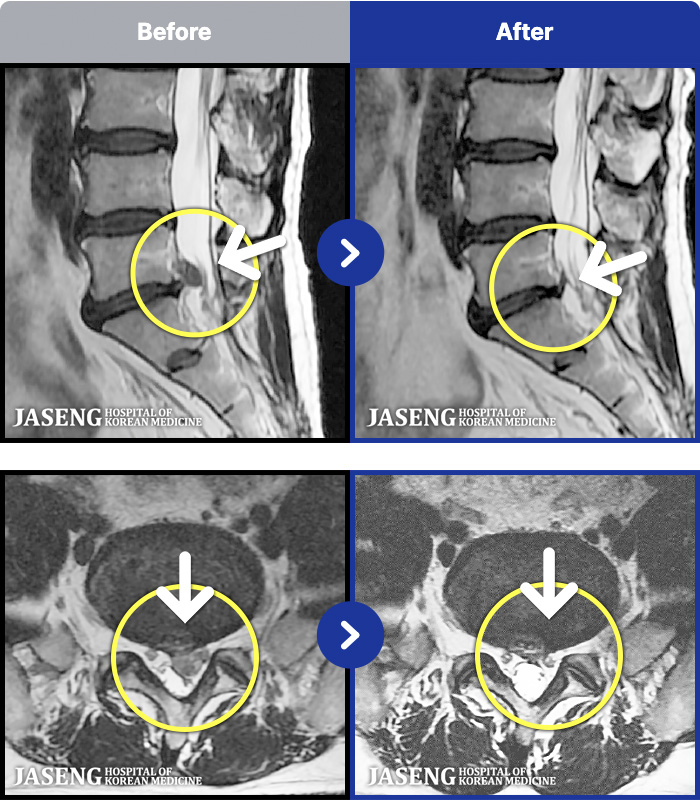

66 MRI ũ ʸ Ȯϼ.